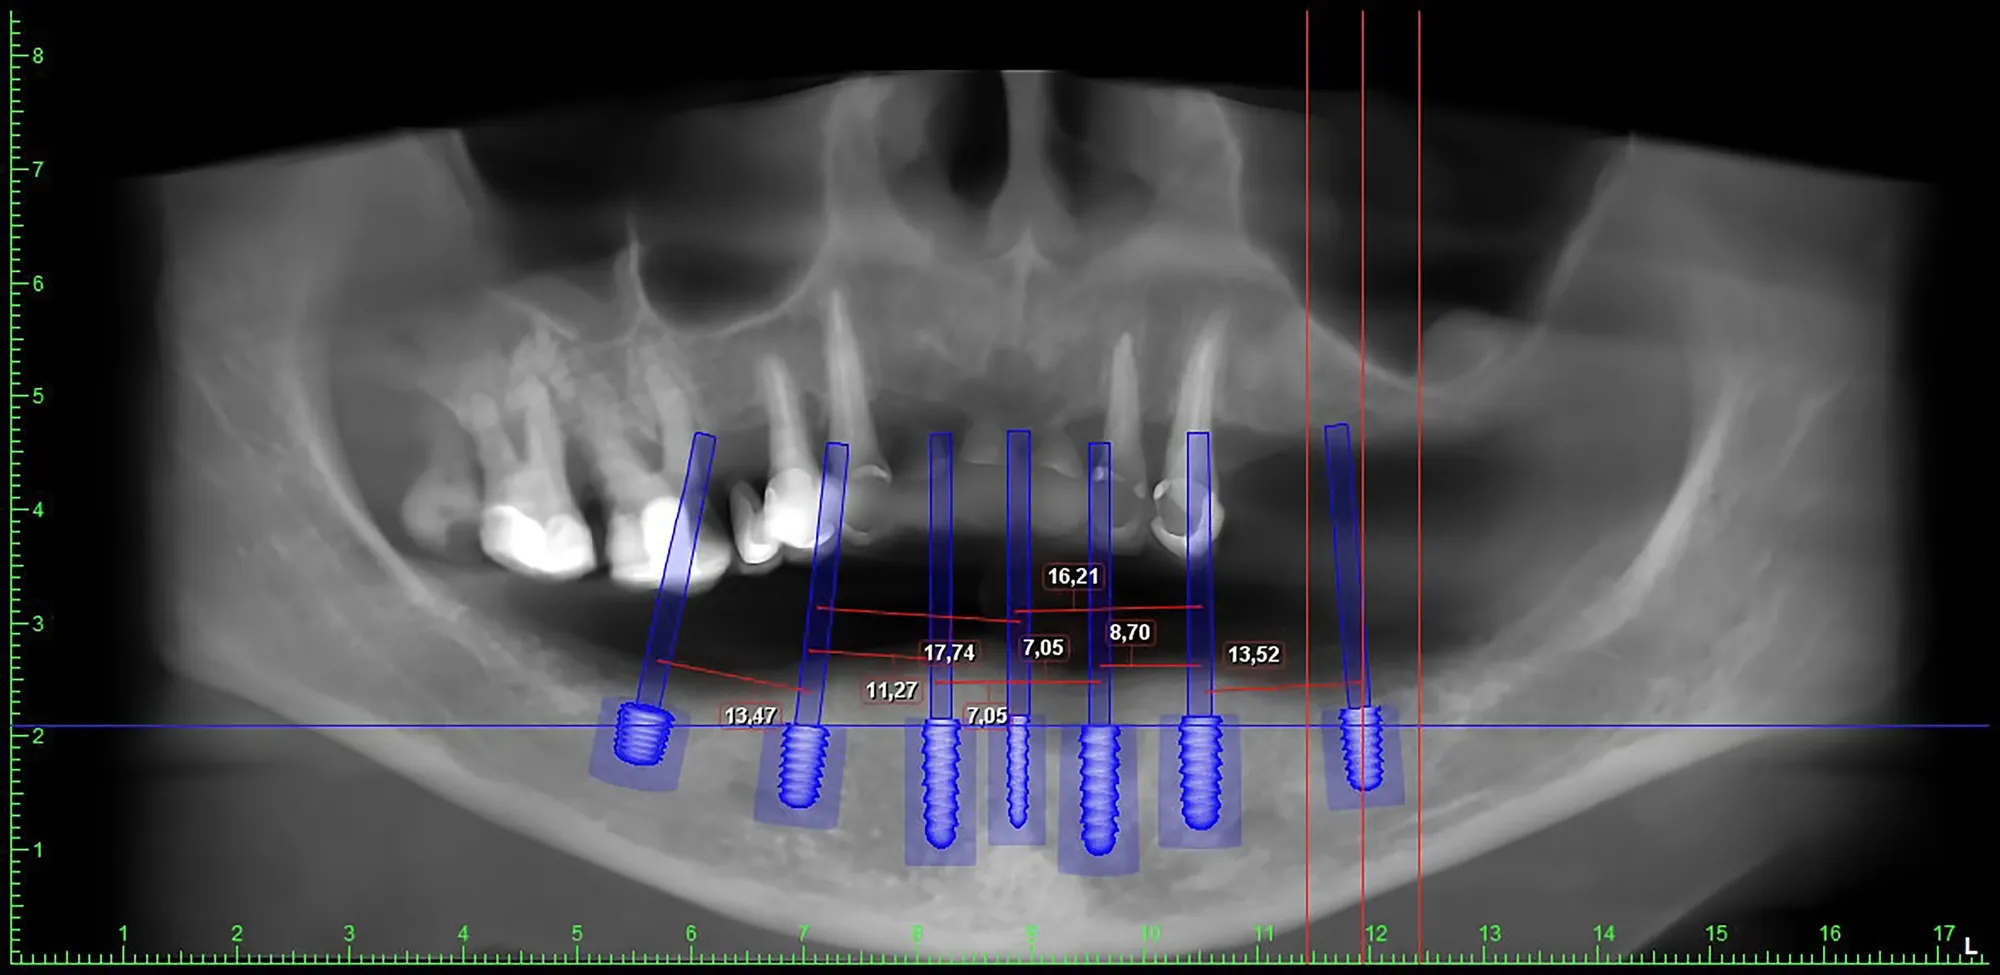

- Acquisiamo una TAC 3D dell’osso del paziente.

- Sovrapponiamo le due immagini grazie a un software specifico.

- Pianifichiamo virtualmente l’intervento decidendo il numero, la posizione e l’angolazione ideale degli impianti.

Questa mascherina guida con estrema precisione l’inserimento degli impianti nella bocca reale del paziente, seguendo esattamente quanto progettato al computer.

- ✅ Precisione millimetrica nel posizionamento degli impianti

- ✅ Pianificazione pre-operatoria dettagliata e su misura